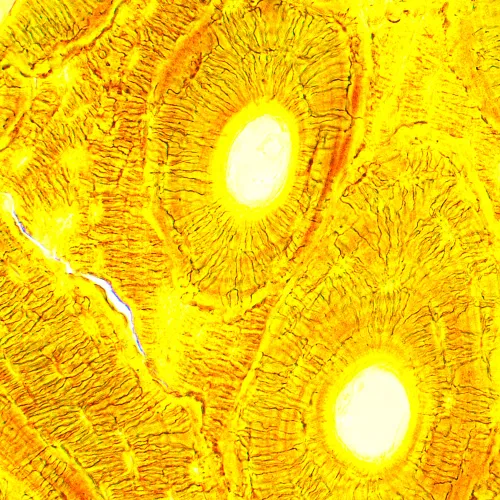

Биологичният микроскоп MAGUS Bio 250T е професионален уред за наблюдение на биологични образци с пропускана светлина. Основният метод за изследване е методът на светлото поле (готов за употреба). Също са достъпни методите на тъмно поле, поляризация и фазов контраст, но за тях са необходими допълнителни принадлежности за микроскоп. Микроскопът е отличен за лабораторни и изследователски наблюдения в медицината, фармацевтиката, криминалистиката, селското стопанство и други области.

Планахроматичните обективи осигуряват ясно, контрастно и детайлно изображение с минимално изкривяване. Увеличението с приложените обективи и окуляри е в диапазона от 40 до 1000x, а горната граница може да се увеличи с допълнителни окуляри. Оптичните елементи са коригирани до безкрайност, което означава, че на оптичния път могат да се монтират допълнителни принадлежности.